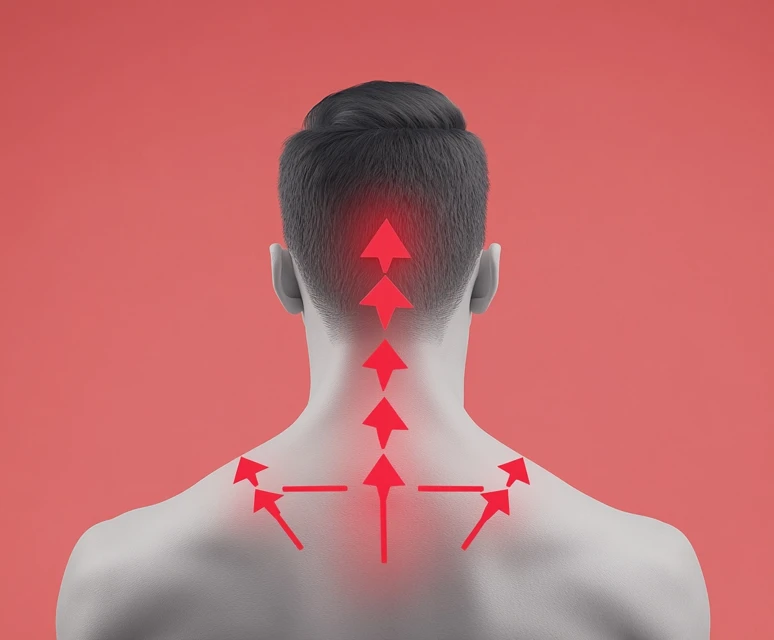

- 목의 통증: 목디스크의 가장 일반적인 초기 증상은 목의 통증입니다. 이 통증은 지속적일 수도 있고, 특정 자세를 취할 때 더욱 심해질 수 있습니다. 일반적인 근육통과는 다르게, 목의 통증은 종종 뻣뻣함과 함께 오는 경우가 많습니다.

- 어깨와 팔의 방사통: 목디스크로 인한 신경 압박으로 인해 어깨나 팔로 방사되는 통증을 느낄 수 있습니다. 이러한 방사통은 날카롭거나 찌릿한 느낌이 들며, 특히 팔을 움직일 때 그 강도가 증가할 수 있습니다.

- 머리의 통증: 목디스크의 통증은 두통으로도 이어질 수 있습니다. 특히 긴장성 두통과 비슷한 유형의 두통이 발생할 수 있으며, 이는 경추가 제대로 기능하지 못할 때 나타납니다.